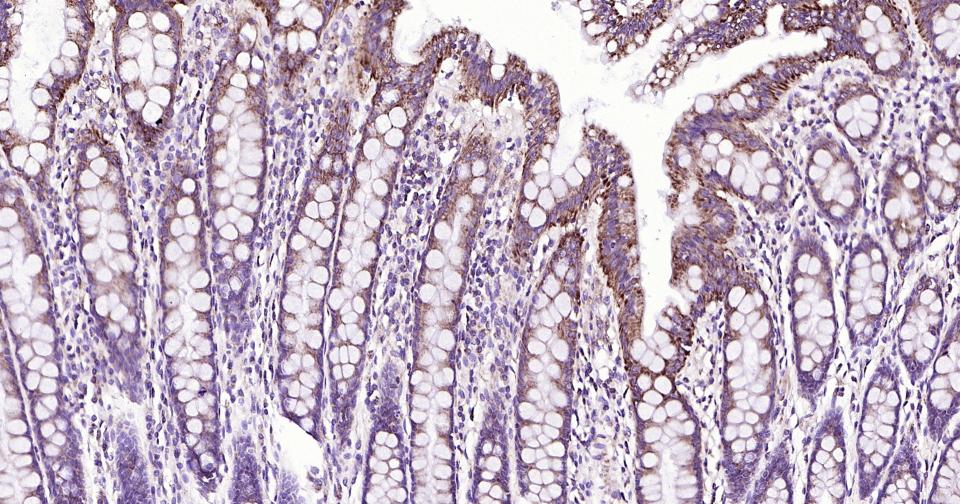

Paraformaldehyde-fixed, paraffin embedded Human Colon; Antigen retrieval by boiling in sodium citrate buffer (pH6.0) for 15 min; Antibody incubation with Bak Monoclonal Antibody, Unconjugated(bsm-61174R) at 1:200 overnight at 4°C, followed by conjugation to the SP Kit (Rabbit, SP-0023) and DAB (C-0010) staining.